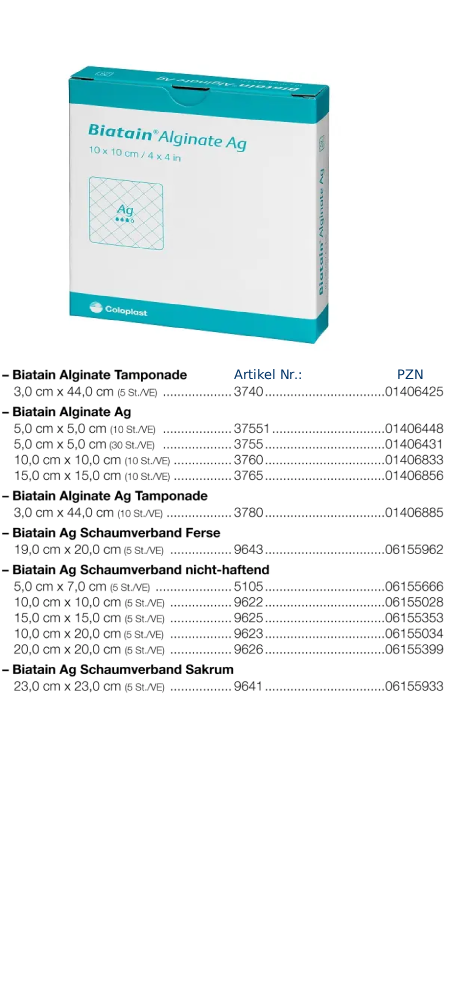

Biatain Alginate (COLOPLAST)

Biatain Alginate Tamponade (COLOPLAST)

Der weiche und gut applizierbare Biatain Alginate ![]() (3) Alginatverband ist durch den Zusatz von Calciumalginat und Carboxymethylcellulose (CMC) ein sehr stark absorbierendes Produkt. Hohe Reißfestigkeit und hohe Gelintegrität zeichnen Biatain Alginate zusätzlich aus.

(3) Alginatverband ist durch den Zusatz von Calciumalginat und Carboxymethylcellulose (CMC) ein sehr stark absorbierendes Produkt. Hohe Reißfestigkeit und hohe Gelintegrität zeichnen Biatain Alginate zusätzlich aus.